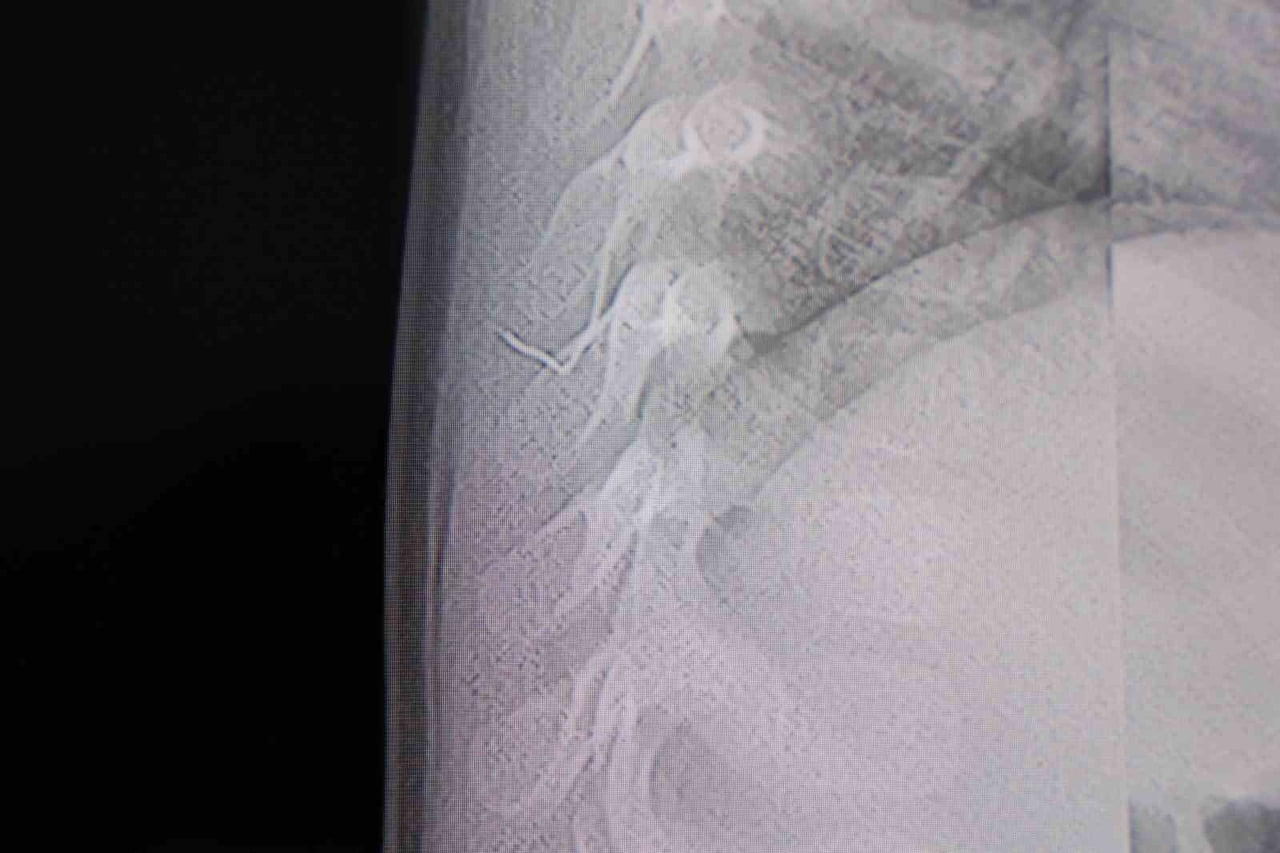

HG Hospital Beyin ve Sinir Cerrahisi Uzmanı Prof. Dr. İdris Altun tarafından yapılan tetkikler, cismin cilt altında, omurilik kanalına çok yakın bir bölgede ve akciğer zarına doğru ilerlediğini gösterdi. Hasta, genel anestezi uygulanmadan, lokal anestezi ve sedasyon eşliğinde ameliyata alındı ve yabancı cisim tamamen çıkarıldı. Çıkarılan cismin, ince zımba teline benzer metal bir tel olduğu ve yaklaşık 2 santimetre uzunluğunda bulunduğu tespit edildi. Hasta gerekli kontrollerin ardından aynı gün taburcu edildi.

Prof. Dr. İdris Altun şöyle dedi: "Sırtında yabancı bir cisim olduğu söylenmiş ancak çıkarılamayacağı ve 8 yaşına kadar beklenmesi gerektiği ifade edilmişti. Bize başvurduğunda yaptığımız tetkiklerde, cilt altında, omurilik kanalına çok yakın ve akciğer zarına doğru ilerleyen bir yabancı cisim tespit ettik. Hastamızı tamamen uyutmadan, lokal anestezi ve sedasyon eşliğinde müdahale ederek lezyonu tamamen çıkardık. Çıkardığımız cismin ince zımba teline benzer, yaklaşık 2 santimetre uzunluğunda metal bir tel olduğunu gördük. Bu yabancı cisim alınmasaydı, bölgede enfeksiyon gelişebilirdi. Enfeksiyon sonucu omurilik kanalında ciddi hasarlar oluşabilir, çocuk büyüdükçe cismin hareket etmesine bağlı olarak omurilikte zedelenmeler meydana gelebilirdi. Ayrıca yana doğru ilerleyerek akciğer zarına ve akciğere batma riski vardı. Bu da enfeksiyona ve ilerleyen süreçte tümörle karışabilecek tablolara neden olabilirdi. Şu an hastamız gayet sağlıklı. Gerekli kontrolleri yaptık ve aynı gün taburcu ettik".